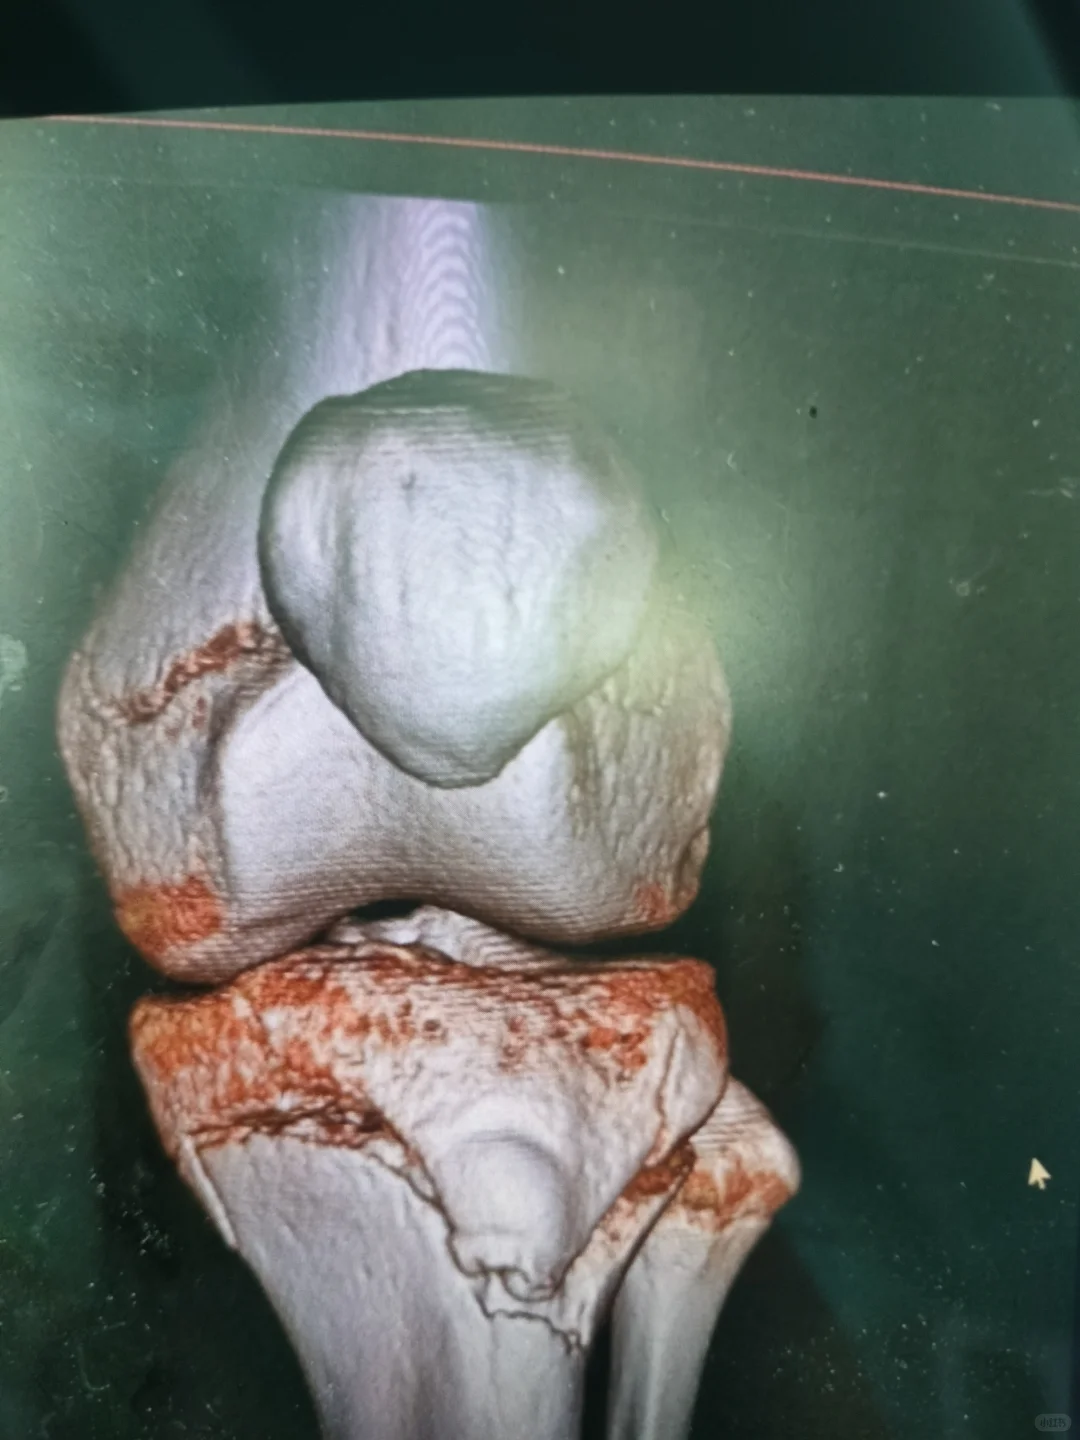

医生根据ct结果总结左胫骨平台见骨折线,其断端无分离及成角,周围软组织稍肿胀,余左膝关节诸骨未见骨折及脱位征